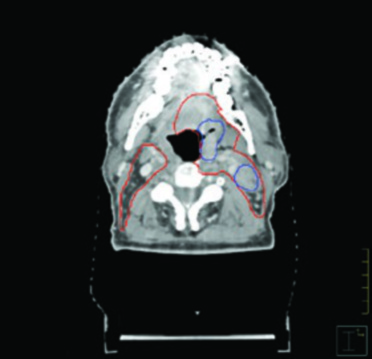

Las figuras de este capítulo ilustran casos reales que ejemplifican los principios de delineación discutidos. El caso de carcinoma amigdalino VPH-negativo cT4N2 demuestra la necesidad de cobertura hasta las láminas pterigoideas e inclusión del nivel IB ipsilateral por invasión de la lengua oral. Observe cómo el GTV (azul) y el CTV (rojo) se adaptan a las barreras anatómicas, respetando hueso y aire mientras se expanden generosamente hacia los tejidos blandos.